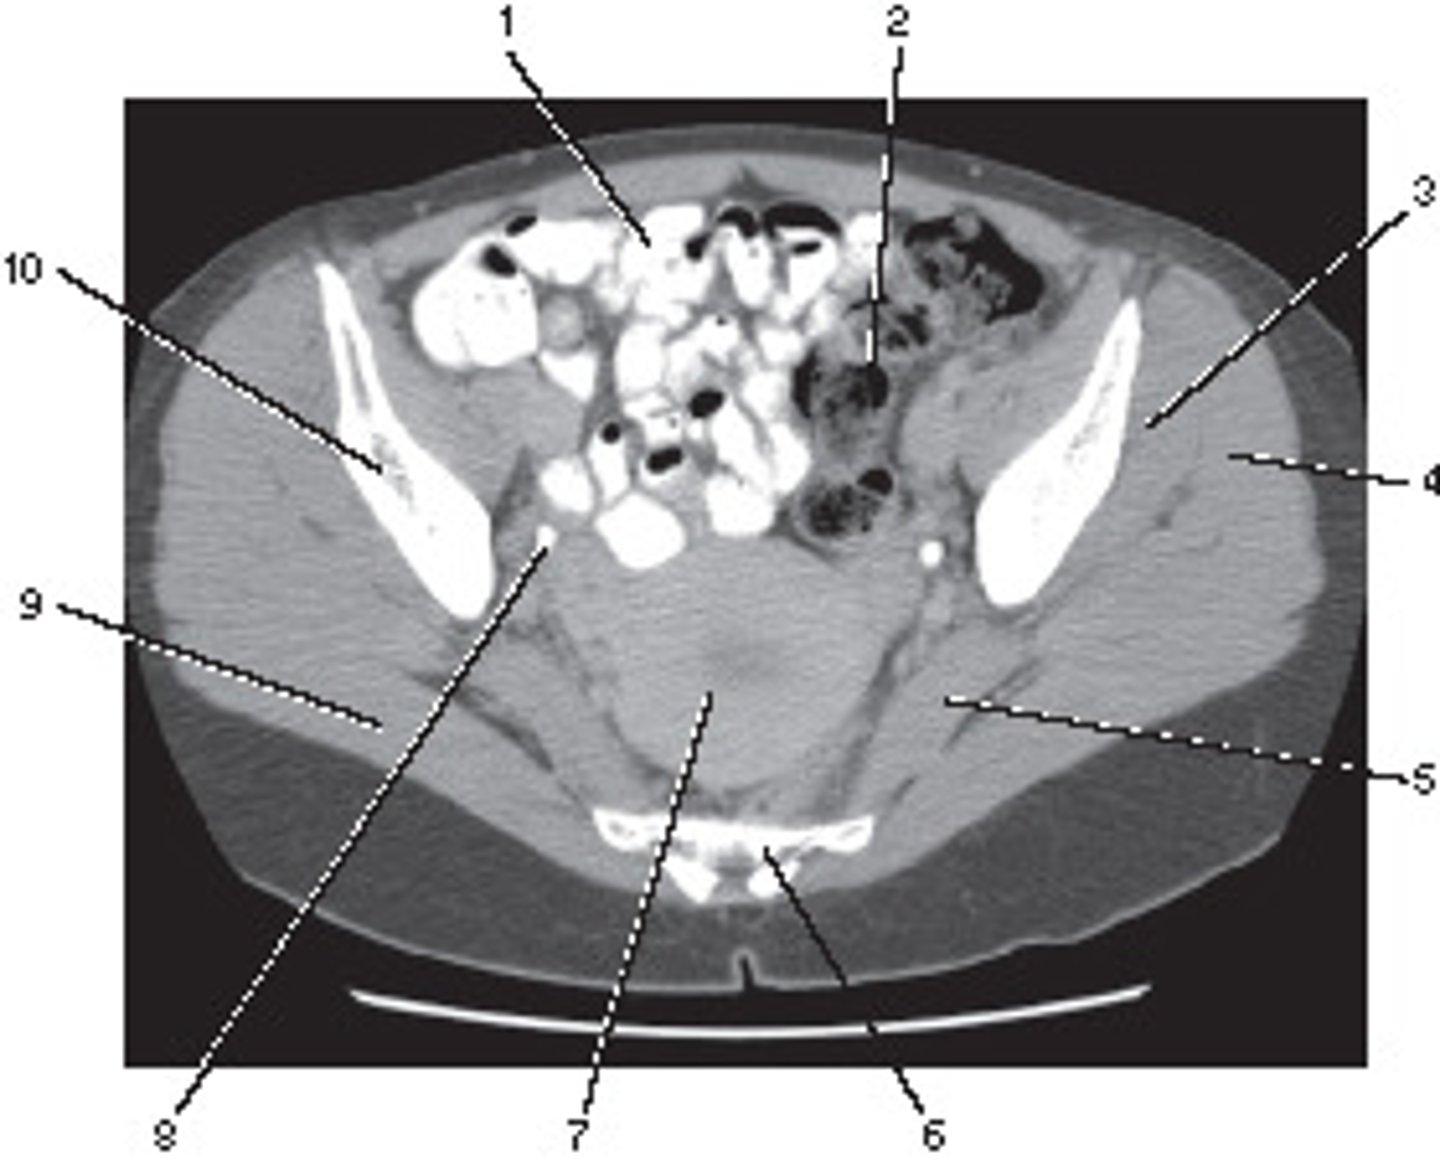

Inferior Vena Cava

Number 8 corresponds to which of the following?

<p>Number 8 corresponds to which of the following?</p>

Spleen

Number 4 corresponds to which of the following?

<p>Number 4 corresponds to which of the following?</p>

Number 6 corresponds to which of the following?

<p>Number 6 corresponds to which of the following?</p>

9

Psoas Major Muscle

Number 2 corresponds to which of the following?

<p>Number 2 corresponds to which of the following?</p>

Axial

This image displays what anatomic plane?

<p>This image displays what anatomic plane?</p>

Ilium